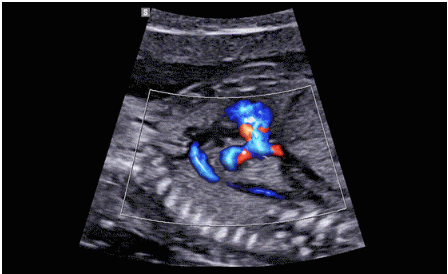

CrystalLive?是三星最新的超聲成像引擎,同時(shí)增強(qiáng)了2D圖像處理能力、3D渲染能力和彩色信號處理能力,能夠在復(fù)雜情況下提供出色的圖像性能,具備檢測外周血管、微循環(huán)血流的能力。

2D成像方面,Hera i10集成了包括ShadowHDR?、HQ-Vision?、ClearVision等多項(xiàng)具有三星“血統(tǒng)”的技術(shù),加強(qiáng)了圖像的陰影抑制、減少偽影、緩和模糊區(qū)。